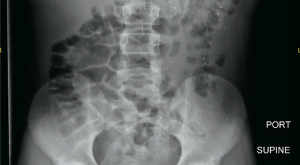

An 11-year-old male presents to the emergency department (ED) with complaint of 2 days of focal, crampy, periumbilical abdominal pain associated with anorexia, fever, and 1 episode of emesis. What's the diagnosis?